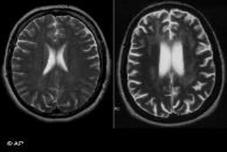

Ziabaties K Natije Me Yaaddasht Pr Manfi Asraat

محققین کا کہنا ہے کہ ذیابیطس کے دائمی مریضوں میں ادویات کے ذریعے خون میں شوگر کی سطح گھٹانے سے ان کے دماغ کا حصہ محفوظ رکھنے میں مدد ملتی ہے مگر اس سے یادداشت کی کمزوری کے عمل کو روکنے میں کوئی فرق ن...